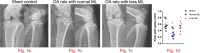

Results: Our radiographs showed that joint space was significantly enlarged in rats with less mechanical loading. Moreover, cartilage destruction was attenuated in the less mechanical loading group with lower histological damage scores, and lower expression of a disintegrin and metalloproteinase with thrombospondin motifs (ADAMTS)-5, matrix metalloproteinase (MMP)-3, and MMP-13. In addition, subchondral bone abnormal changes were ameliorated in OA rats with less mechanical loading, as reduced bone mineral density (BMD), bone volume/tissue volume (BV/TV), and number of osteophytes and osteoclasts in the subchondral bone were observed. Finally, the level of serum inflammatory cytokines was significantly downregulated in the less mechanical loading group compared with the normal mechanical loading group, as well as the expression of NACHT, LRR, and PYD domains-containing protein 3 (NLRP3), caspase-1, and interleukin 1β (IL-1β) in the cartilage.